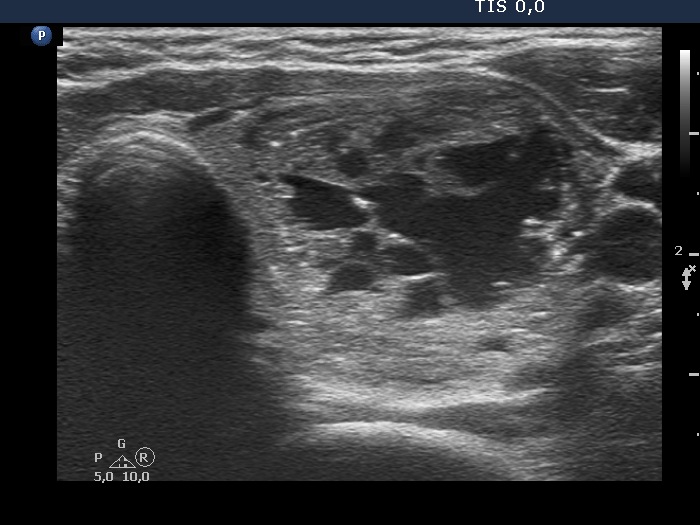

Ultrasonography. The thyroid was echonormal. There was a nodule presenting coarse calcification along its ventral surface. There was a spongiform-type cyst in the left lobe. The nodule has numerous echogenic figures most of them were caused clearly by posterior back wall enhancement.